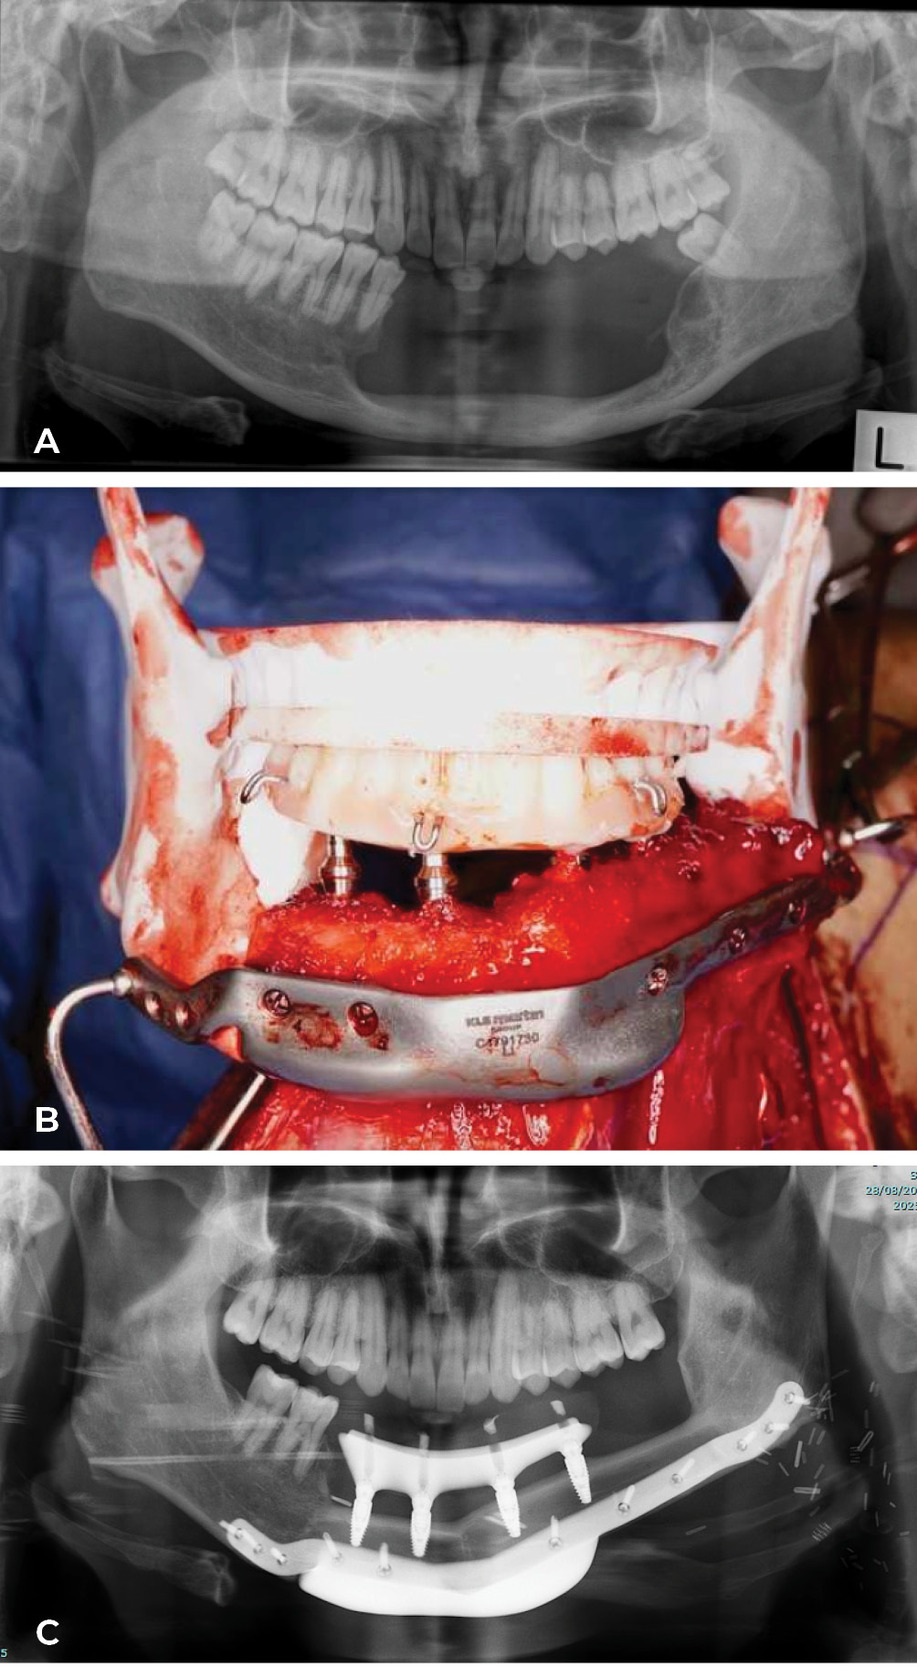

Today the ‘Model T Ford’ has changed shape at the Royal Melbourne Hospital. The computer (3D printing) is used to generate a replica of the fibula, selected after angiography, plus the patient’s jaw segment to be removed. Key osteotomies, with their site and angle, are designed on the fibula replica to reconstruct the shape of the jaw. In a case Ian watched in theatre, the fibula reshaping was done and fixed with plates while still attached in the leg. The fibula was detached, fixed in the mandible and dentures inserted at predetermined sites to match the occlusion of the upper jaw. The patient went to theatre with a tumour in the jaw and woke with a new set of teeth! A case done by Anand Ramakrishnan, Head of Plastic and Reconstructive Surgery and the team at the Royal Melbourne Hospital, is shown in Case 6 (Figure 26 and Figure 27). Combined with maxillofacial and oncological surgeons they now provide four separate teams a week at the Royal Melbourne Hospital to treat facial malignancy. In the last 10 years their total of fibula jaw reconstructions is 198.